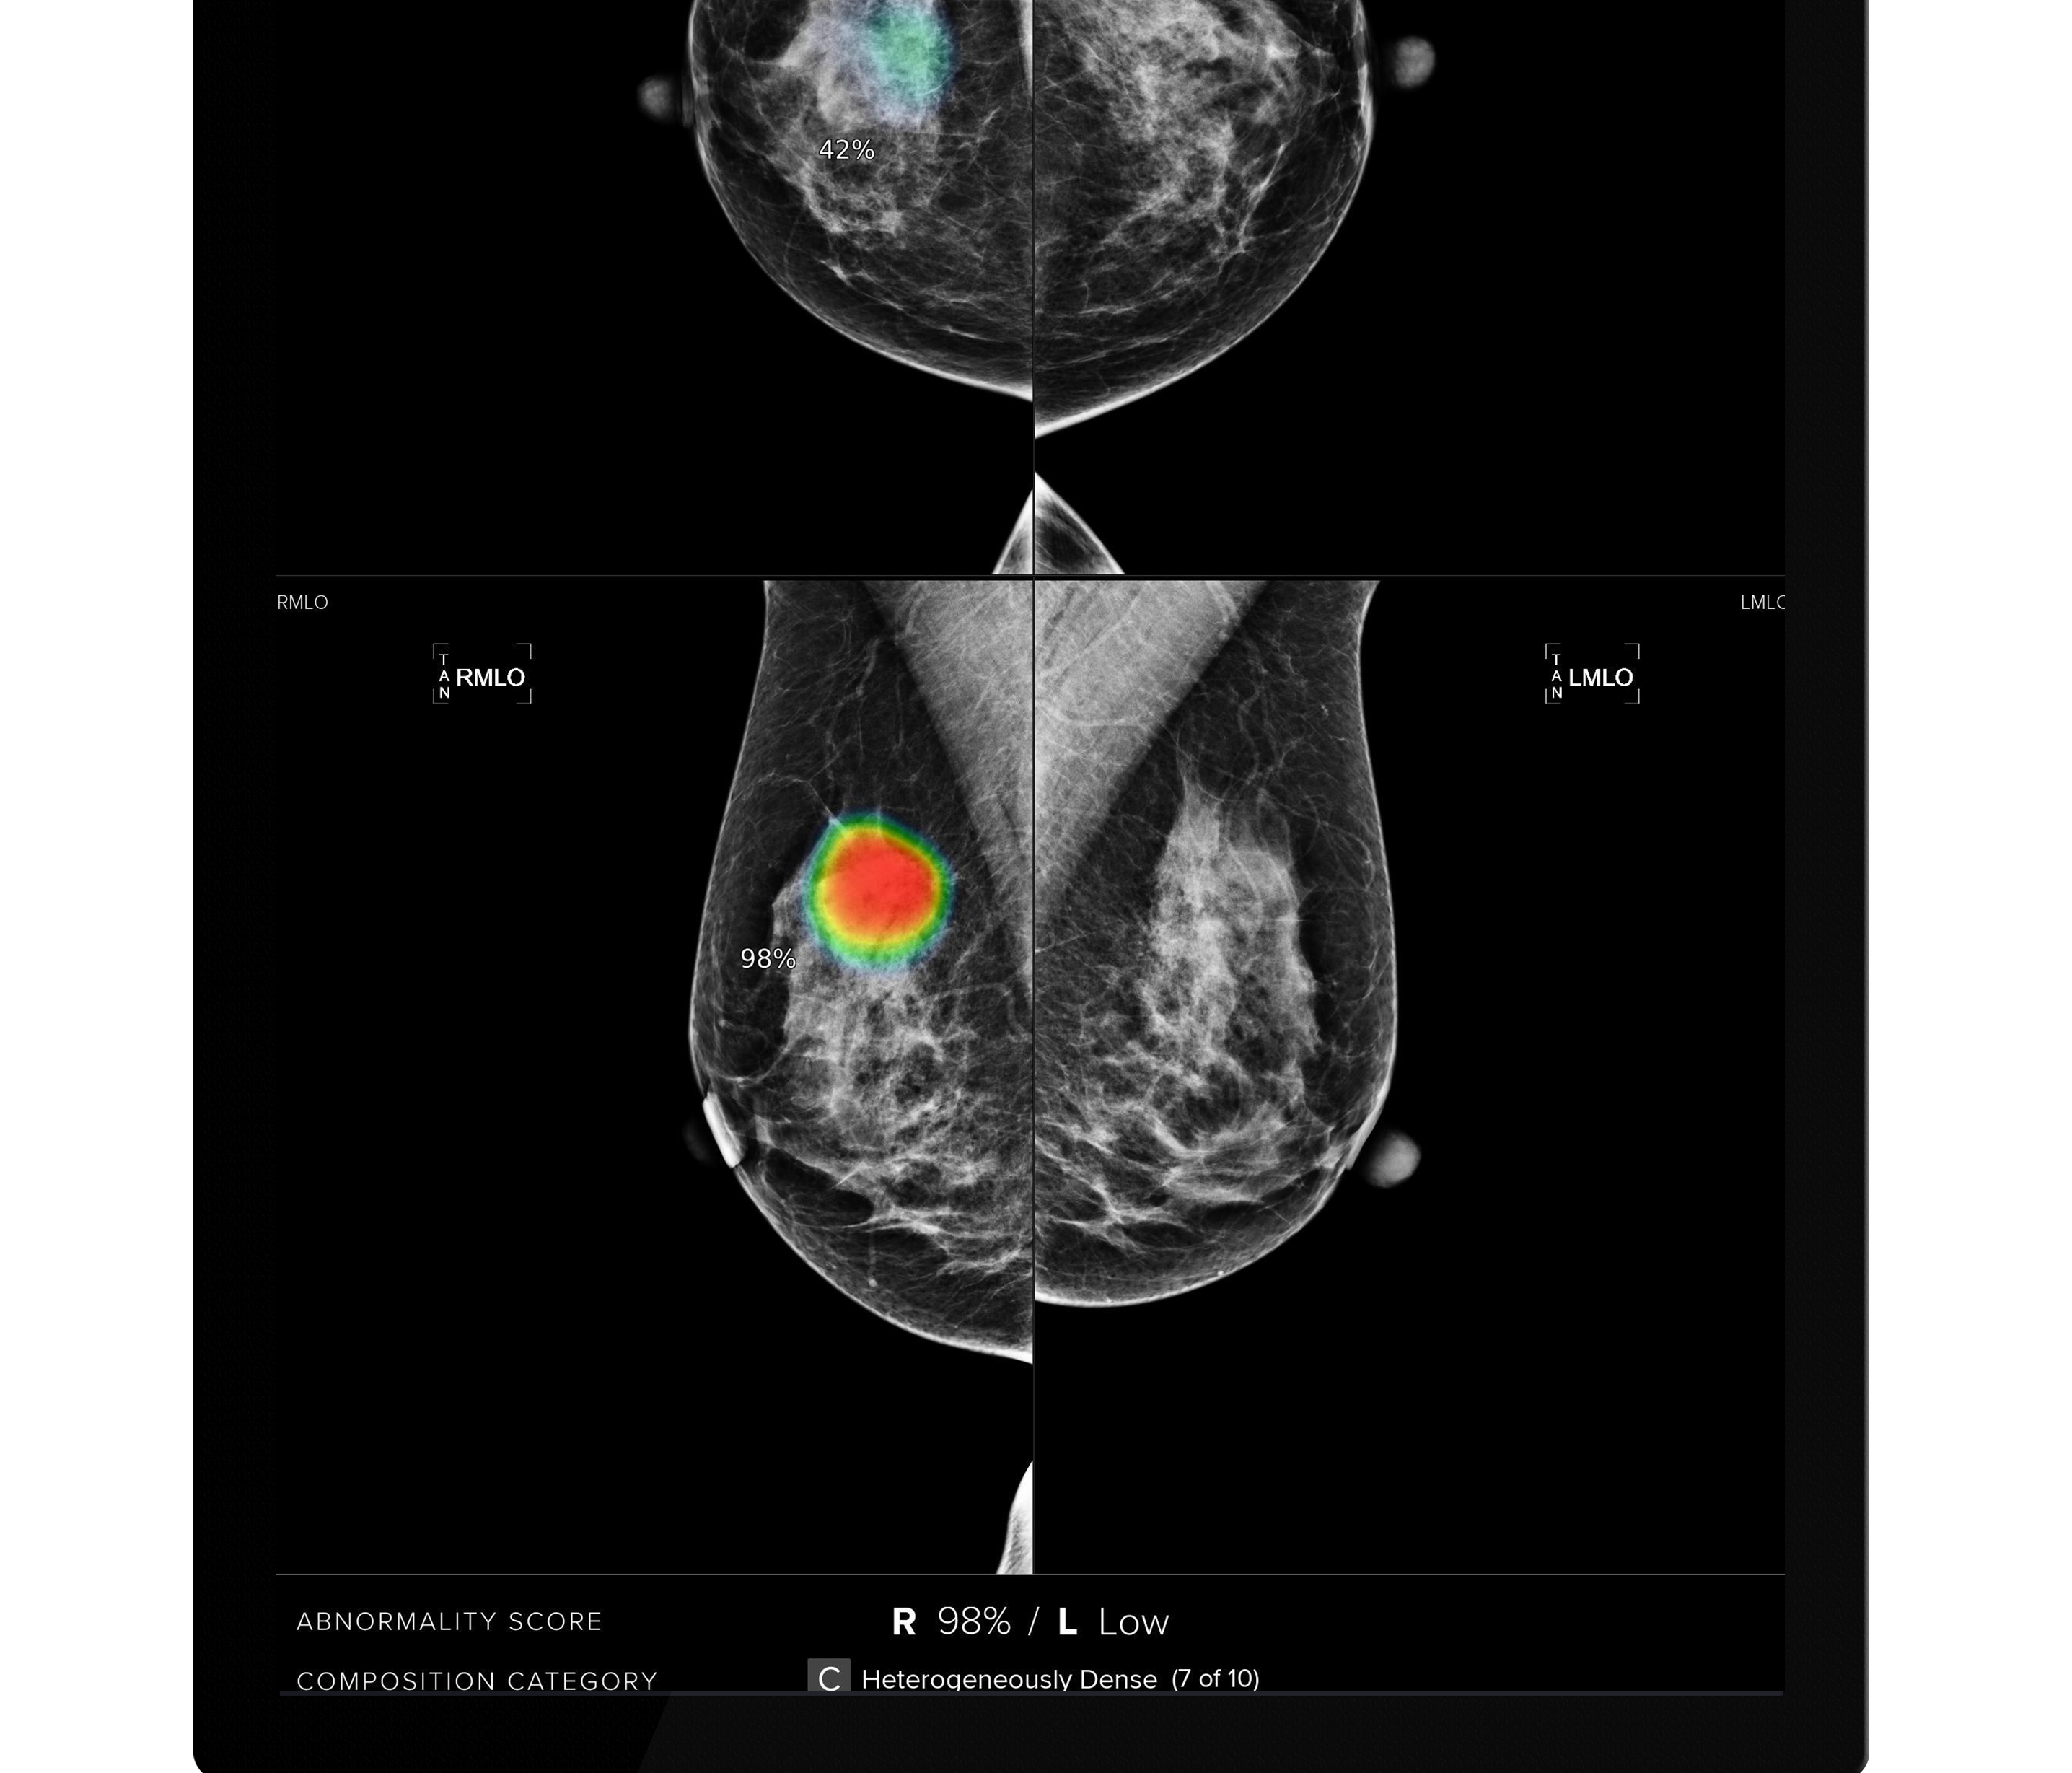

루닛은 이번 계약에 따라 홍콩 영상센터인 HKWI(Hong Kong Women’s Imaging) 병원과 몽골 국립암센터(National Cancer Center of Mongolia) 및 몽골 울란바토르 소재 의료기관인 Breast Clinic of Ulaanbaatar에 유방촬영술 AI 영상분석 솔루션 ‘루닛 인사이트 MMG’를 공급하게 됐다.